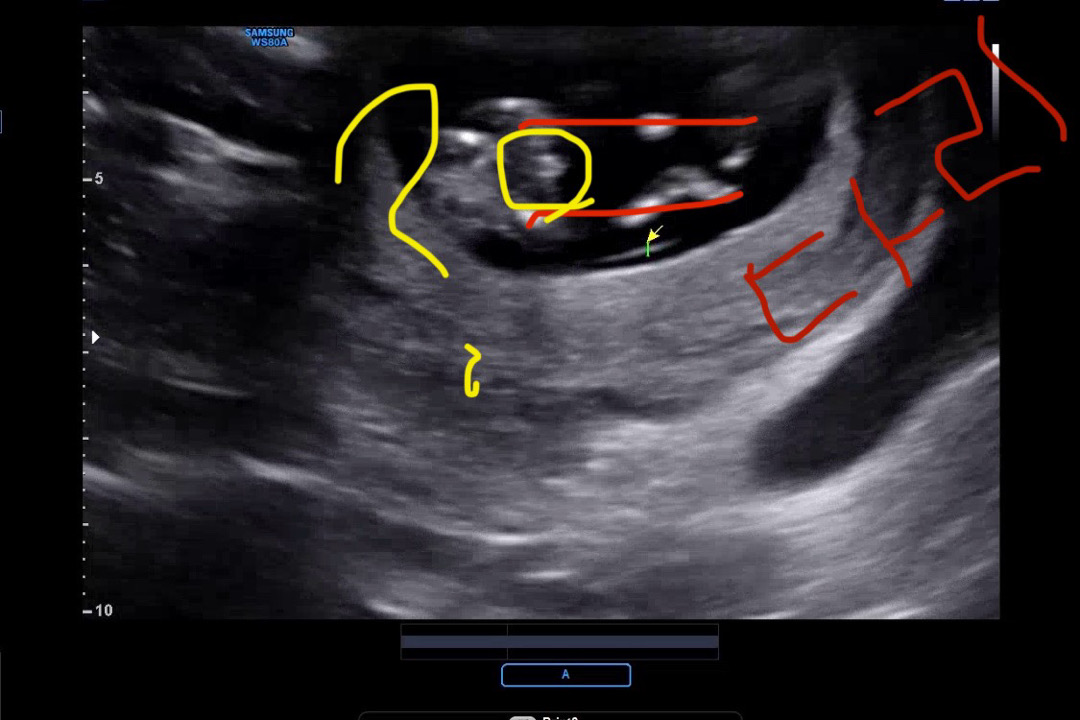

다리 사이 🌶️ 가능성..?

12주 3일째에 초음파 보고 왔는데 등 돌리고 있어서 각도법 유추해볼 자세도 못보고ㅠㅠ 척추뼈만 열심히 보고 왔네여 초음파 영상 찰나에 다리사이가 찍혔는데 요거 🌶️로 클 가능성 있을까요……..?